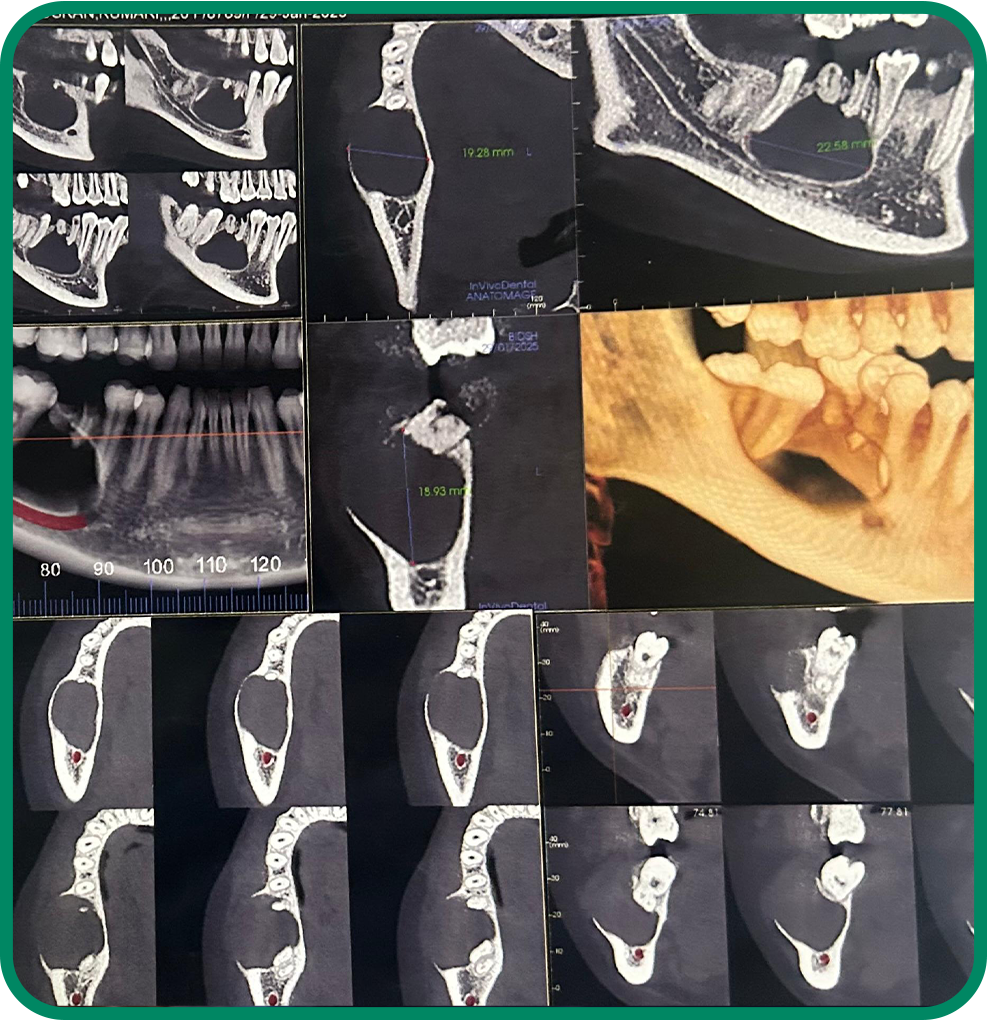

Zygomatic Implants

Specialized implant solution for patients with low bone density, providing strong support without the need for bone grafting.

TMJ Disorder Diagnosis & Treatment

TMJ Disorder Diagnosis & Treatment

Oral Pathologies (Cysts & Tumors)